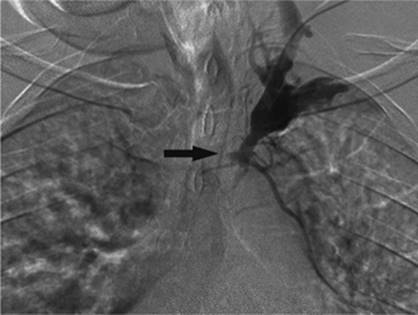

Transjugular intrahepatic portacaval shunting (TIPS) was first conceived of and performed in dogs in 1969 by Josef Rosch et al. (36). The first human case of percutaneous TIPS was reported in 1988 (37). It is an effective nonsurgical and nonendoscopic means to control variceal bleeding by decompressing the portal venous system (38). A CT scan, ultrasound, or MRI is recommended to evaluate for patency of the portal vein as well as exclude hepatic neoplasm and evaluate for other anatomic considerations. The usual laboratory studies to check for hematocrit and coagulopathy should also be performed. IV antibiotics should be administered prior to the procedure. The technique consists of a percutaneous approach, usually ultrasound-guided canalization of the right internal jugular vein. From this approach, access is gained to the hepatic veins and pressure measurements are made from the portal vein using a wedged technique to the right atrium. A hepatic venogram is performed, followed by angiogram of the portal vein, using carbon dioxide and either a wedged technique or puncture of the hepatic parenchyma through the jugular access. Passage of a long curved needle is then performed from a satisfactory location in the hepatic vein, usually the right hepatic vein, into the identified location in the intrahepatic portion of the portal vein or its branches. Direct pressure measurements are made using the transjugular pathway (Fig. 35.20). If acceptable, balloon angioplasty of the intrahepatic tract between the hepatic vein and the portal vein is then performed. A stent, usually covered, is deployed from the portal vein to the hepatic vein through the tract to keep it patent and prevent hepatic recoil and restenosis (Fig. 35.21). Repeat pressure measurements are performed to confirm satisfactory pressures have been reached. Any additional adjustments that need to be made to the stent can be performed at this time, as well as embolization of varices if indicated.

Figure 35.20. Patient with cirrhosis undergoing a transjugular intrahepatic, portacaval shunting (TIPS) procedure. Catheter (white arrow) is positioned from a hepatic venous approach, through the hepatic parenchyma into the portal vein (black arrow). (Image courtesy of Harry K. Meisenbach, MD.)